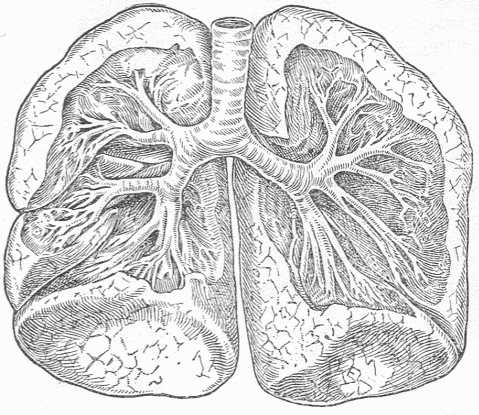

Fig. 6—Photograph Of A Section Of The Lung Of A Mouse. x x are the air tubes or bronchi which communicate with all of the small spaces. On the walls of the partitions there is a close network of blood vessels which are separated from the air in the spaces by a thin membrane.

The external surface passes into the interior of the body forming two surfaces, one of which, the intestinal canal, communicates in two places, at the mouth and anus, with the external surface; and the other, the genito-urinary surface, which communicates with the external surface at one place only. The surface of the intestinal canal is much greater in extent than the surface on the exterior, and finds enormous extensions in the lungs and in the great glands such as the liver and pancreas, which communicate with it by means of their ducts. The extent of surface within the lungs is estimated at ninety-eight square yards, which is due to the extensive infoldings of the surface [Fig 6], just as a large surface of thin cloth can, by folding, be compressed into a small space. The intestinal canal from the mouth to the anus is thirty feet long, the circumference varies greatly, but an average circumference of three inches may safely be assumed, which would give between seven and eight square feet of surface, this being many times multiplied by adding the surfaces of the glands which are connected with it. A diagram of the microscopic structure of the intestinal wall shows how little appreciation of the extent of surface the examination with the naked eye gives [Fig. 7]. By means of the intestinal canal food or substances necessary to provide the energy which the living tissue transforms are introduced. This food is liquefied and so altered by the action of the various fluids formed in the glands of the intestine and poured out on the surface, that it can pass into the interior of the body and become available for the living cells. Various food residues representing either excess of material or material incapable of digestion remain in the intestine, and after undergoing various changes, putrefactive in character, pass from the anus as feces.

By means of the lungs, which represent a part of the surface, the oxygen of the air, which is indispensable for the life of the cells, is taken into the body and carbonic acid removed. The interchange of gases is effected by the blood, which, enclosed in innumerable, small, thin-walled tubes, almost covers the surface, and comes in contact with the air within the lungs, taking from it oxygen and giving to it carbonic acid.

Fig. 10.—The Lungs And Windpipe. Parts of the lungs have been removed to show the branching of the air tubes or bronchi which pass into them. All the tubes and the surfaces of the lungs communicate with the inner surface of the body through the larynx.